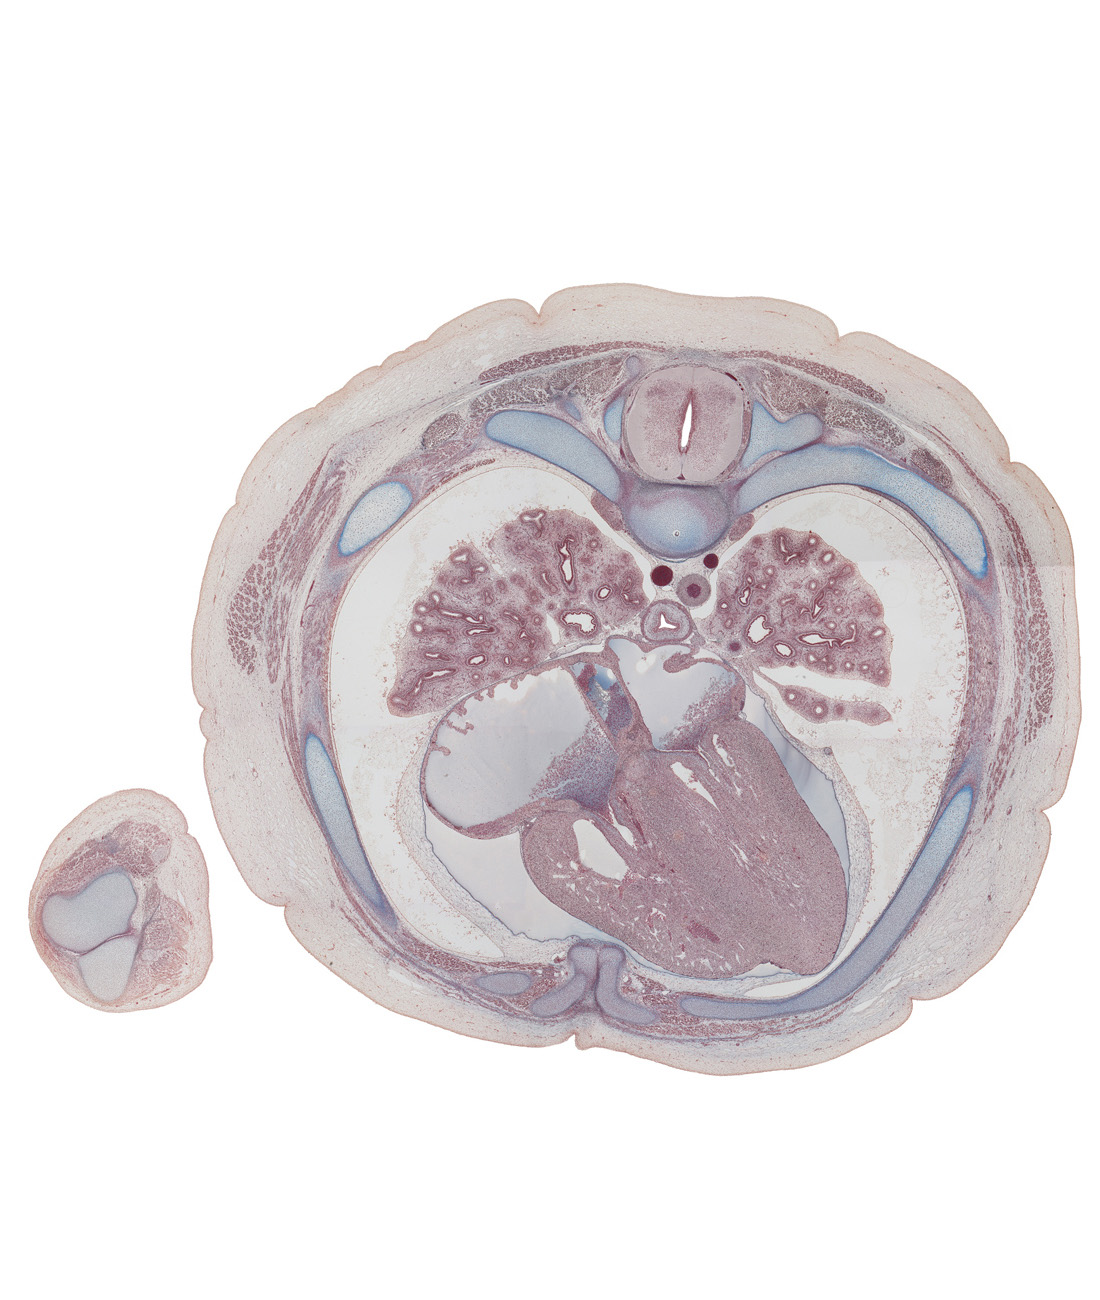

Carnegie Embryo #9226 | Location: 122-01-01

Keywords: T-5 / T-6 interganglion region, T-5 / T-6 intervertebral disc, anterior interventricular sulcus, anterior papillary muscle in right ventricle, aorta, atrioventricular sulcus, dorsal funiculus, edge of lingula of upper lobe of left lung, esophagus, interatrial septum, lateral funiculus, left atrioventricular (mitral) valve, left phrenic nerve, lower lobe of left lung, lower lobe of right lung, middle lobe of right lung, pericardial cavity, pericardial sac, rib 5, rib 6, rib 6 (costal cartilage), right atrioventricular (tricuspid) valve opening, right lower pulmonary vein, ventral funiculus

Source: The Virtual Human Embryo.